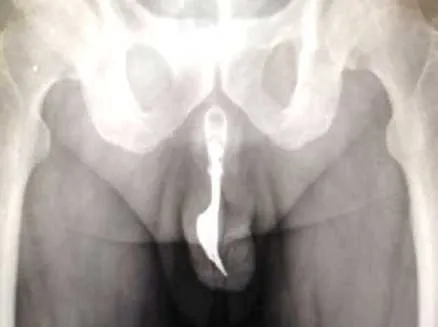

"Appetito" sessualeSi infila una forchetta di 10 cm nel pene, operato d'urgenza un 70enne10 marzo 2020